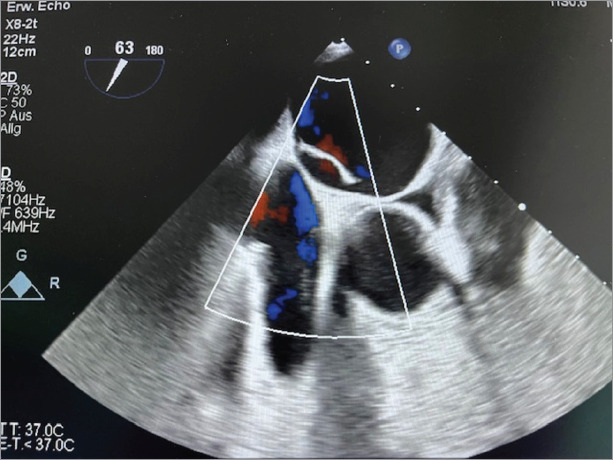

Double Atrial Septum With Interatrial Space in Patients Experiencing Ischemic Attack.

双房间隔伴房间隙与缺血性发作的关系。